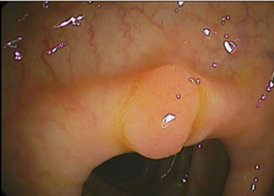

Το εσωτερικό τοίχωμα του εντέρου που ονομάζεται βλεννογόνος αποτελεί μία λεία επιφάνεια που παρουσιάζει αναδιπλώσεις και πτυχές. Όταν σε ένα σημείο ο βλεννογόνος χάσει αυτή την ομαλή εμφάνιση και αποκτήσει ένα οζίδιο που προβάλλει εντός του αυλού του εντέρου, μοιάζει σαν ένα μικρό κουνουπίδι, σαν μανιτάρι, σαν την σταφυλή που έχουμε στο λαιμό μας, τότε ονομάζουμε τη βλάβη αυτή πολύποδα του εντέρου. Επίσης, κάθε παρόμοια εικόνα περιγράφεται ως πολυποειδής διαμόρφωση ή πολυποειδής προβολή του βλεννογόνου. Ο πολύποδας μπορεί να είναι καλοήθης όγκος ή να έχει παρουσιάσει κακοήθη αλλαγή κατά τη διάγνωσή του. Μπορεί, επίσης, να μην αποτελεί πραγματικό νεόπλασμα (δηλαδή όγκο) αλλά πχ. μία φλεγμονή.

Η ανίχνευση ενός πολύποδα βασίζεται στην ενδοσκόπηση κατωτέρου πεπτικού (κολονοσκόπηση, ορθοσιγμοειδοσκόπηση) που παρέχει τη δυνατότητα αναγνώρισης ακόμα και πολύ μικρών πολυπόδων 1-2mm, αλλά και της λήψης βιοψιών ώστε να μελετηθεί ο τύπος τους, να αποκλεισθεί πιθανή κακοήθεια και να καθοριστεί ο τρόπος παρακολούθησης του εντέρου στο μέλλον. Πολλές φορές η διάγνωση ενός πολύποδα είναι τυχαία παρατήρηση κατά τη διενέργεια ενδοσκόπησης για άλλη αιτία. Η διαπίστωση ενός πολύποδα μπορεί να γίνει (εάν το μέγεθός του είναι σχετικά μεγάλο) με ακτινογραφίες παχέος εντέρου μετά από βαριούχο υποκλυσμό. Η τεχνική αυτή προτείνεται όπου δεν μπορεί να πραγματοποιηθεί πλήρης ενδοσκόπηση. Μεγάλοι σε μέγεθος πολύποδες μπορεί να παρατηρηθούν και σε άλλες απεικονιστικές εξετάσεις όπως η αξονική τομογραφία και η μαγνητική τομογραφία. Εάν ο ιατρός το κρίνει αναγκαίο ο περαιτέρω έλεγχος μετά την ανεύρεση ενός μεγάλου πολύποδα μπορεί να συμπληρωθεί με εργαστηριακές εξετάσεις αίματος και κοπράνων. Σε ορισμένες καταστάσεις διενεργείται και ενδοσκόπηση του ανωτέρου πεπτικού (γαστροσκόπηση).

Η θεραπεία των πολυπόδων στηρίζεται στην αφαίρεσή τους (ενδοσκοπική πολυπεκτομή) μέσα από το ενδοσκόπιο με ειδικούς βρόχους ή λαβίδες καυτηρίασης. Ο ασθενής υποβάλλεται σε κολονοσκόπηση με κατάλληλη προετοιμασία και εξαιρετικό καθαρισμό του παχέος εντέρου. Πρέπει να προηγείται έλεγχος της πήξης του αίματος και να τροποποιείται τυχόν αντιπηκτική αγωγή που έχει δοθεί για άλλους ιατρικούς λόγους. Πολύποδες με πλατιά βάση ή μεγάλο μίσχο απαιτούν συχνά την αφαίρεσή τους κατά στάδια με συνδυασμό επεμβατικών τεχνικών. Τοποθετείται πλαστική θηλειά (endoloop) ή μεταλλικά ράμματα (clips), ώστε να αποφευχθεί η αιμορραγία μετά την εκτομή. Συχνά χρειάζεται έγχυση ειδικού αιμοστατικού υγρού κάτω από τον πλατύ πολύποδα ώστε να κοπεί με ασφάλεια διαχωρίζοντας τα υποκείμενα στρώματα του παχέος εντέρου.